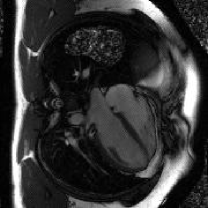

The proposed method is tested on the retrospective cardiac cine dataset OCMR[53]. The detailed information of the dataset is listed in the supplementary file. The acquired data are transformed into the -space domain using the multi-channel NUFFT implementation with golden-angle radial trajectories based on Fibonacci number sequencing. Coil sensitivity maps are derived through the ESPRIT algorithm[54] to enable parallel imaging reconstruction. Different acceleration factors (AFs) are simulated for evaluation, including 21, 13, 8, 5, 3, 2, 1 spokes per frame (AF=9.7, 15.7, 25.5, 40.8, 67.9, 101.9, 203.7).

| NUFFT | GRASP | FMLP | InstantNGP | GridTD | Original |

We select four representative baselines, including the NUFFT that provides direct zero-filled reconstructions without additional processing; the GRASP [39] that incorporates temporal frame grouping, time-averaged coil sensitivity estimation, and TV regularization; the FMLP [41] that employs INR and Fourier feature encoding for reconstruction; and the InstantNGP [24] that employs the multi-resolution hash grid encoding for dynamic MRI reconstruction.

IV-C2 Results

The quantitative results for compressive dynamic MRI reconstruction are shown in Table V. The proposed GridTD method outperforms competing methods across all evaluated settings in PSNR and SSIM metrics. Compared to other unsupervised deep learning methods FMLP and InstantNGP, our GridTD is over 50% faster due to the compact model structure. In Fig. 6, we present some visualizations of the reconstructed MRIs and the corresponding error maps, which demonstrate that GridTD better preserves structural edges and robustly recovers fine details, showing the superiority of our method for dynamic MRI reconstruction. All these results on video SCI, spectral SCI, and dynamic MRI reconstruction validate the strong performance of GridTD, positioning it as a versatile and state-of-the-art approach for compressive imaging reconstruction.